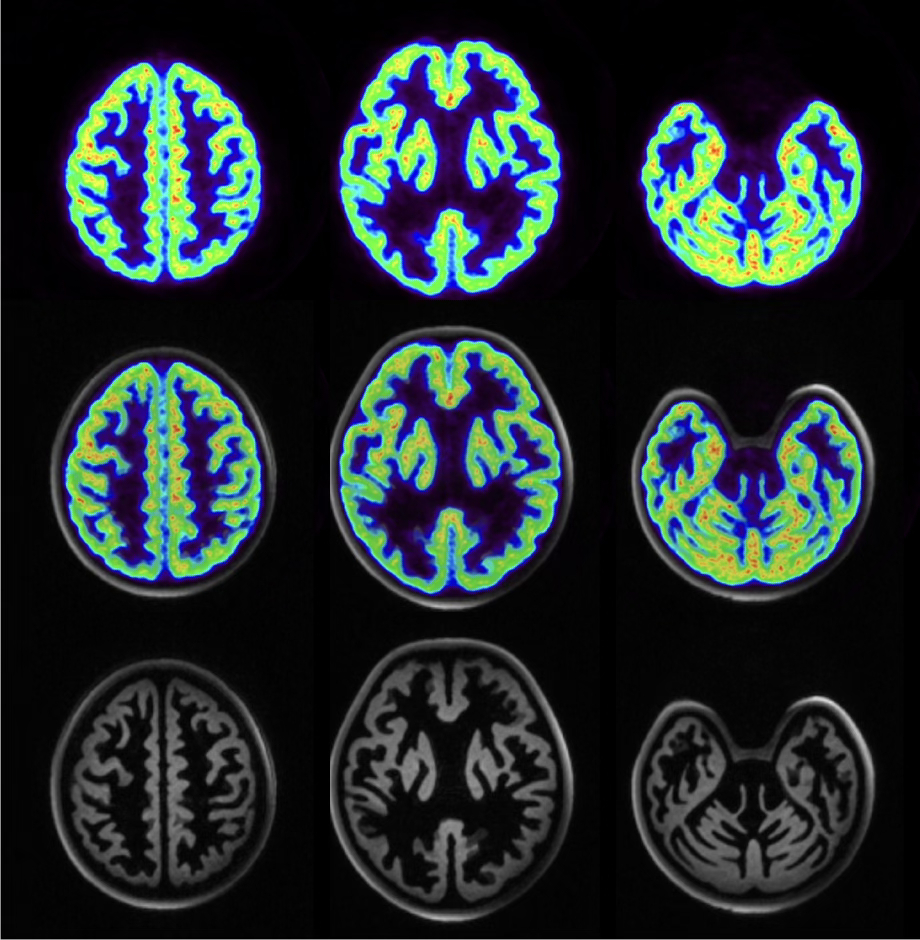

PHYSIK DER MEDIZINISCHEN BILDGEBUNG (INM-4)

Die Forschungs- und Entwicklungsarbeiten unserer Institutsbereiche der Physik der Medizinischen Bildgebung (INM-4) des Instituts für Neurowissenschaften konzentrieren sich auf die Entwicklung, experimentelle Validierung und klinische Prüfung neuer Bildgebungsmethoden des Gehirns.

Jülicher Bildgebungstechnik ermöglicht präzise Einblicke in Struktur und Funktion des menschlichen Gehirn